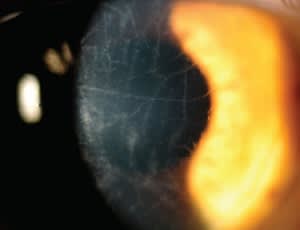

This is a photograph of Lattice corneal dystrophy. This relatively rare stromal dystrophy is autosomal dominant and presents as refractile lines in the anterior stroma during the first decade of life. The lesions that create this lattice pattern consist of amyloid. As this dystrophy progresses, recurrent corneal erosions and scarring of the cornea are common. Treatments consist of bandage contact lenses or penetrating keratoplasty, depending on severity.

The 58-year-old patient featured in the photograph had best-corrected spectacle acuity of 20/200 and 20/40 in the right and left eyes, respectively. She suffered from severe epithelialopathy secondary to her advanced Lattice dystrophy. She was fit into scleral contact lenses (second image) to mask her irregularity and bandage her anterior surface. With the scleral lenses in place her acuity was 20/40 and 20/25 in the right and left eyes, respectively.